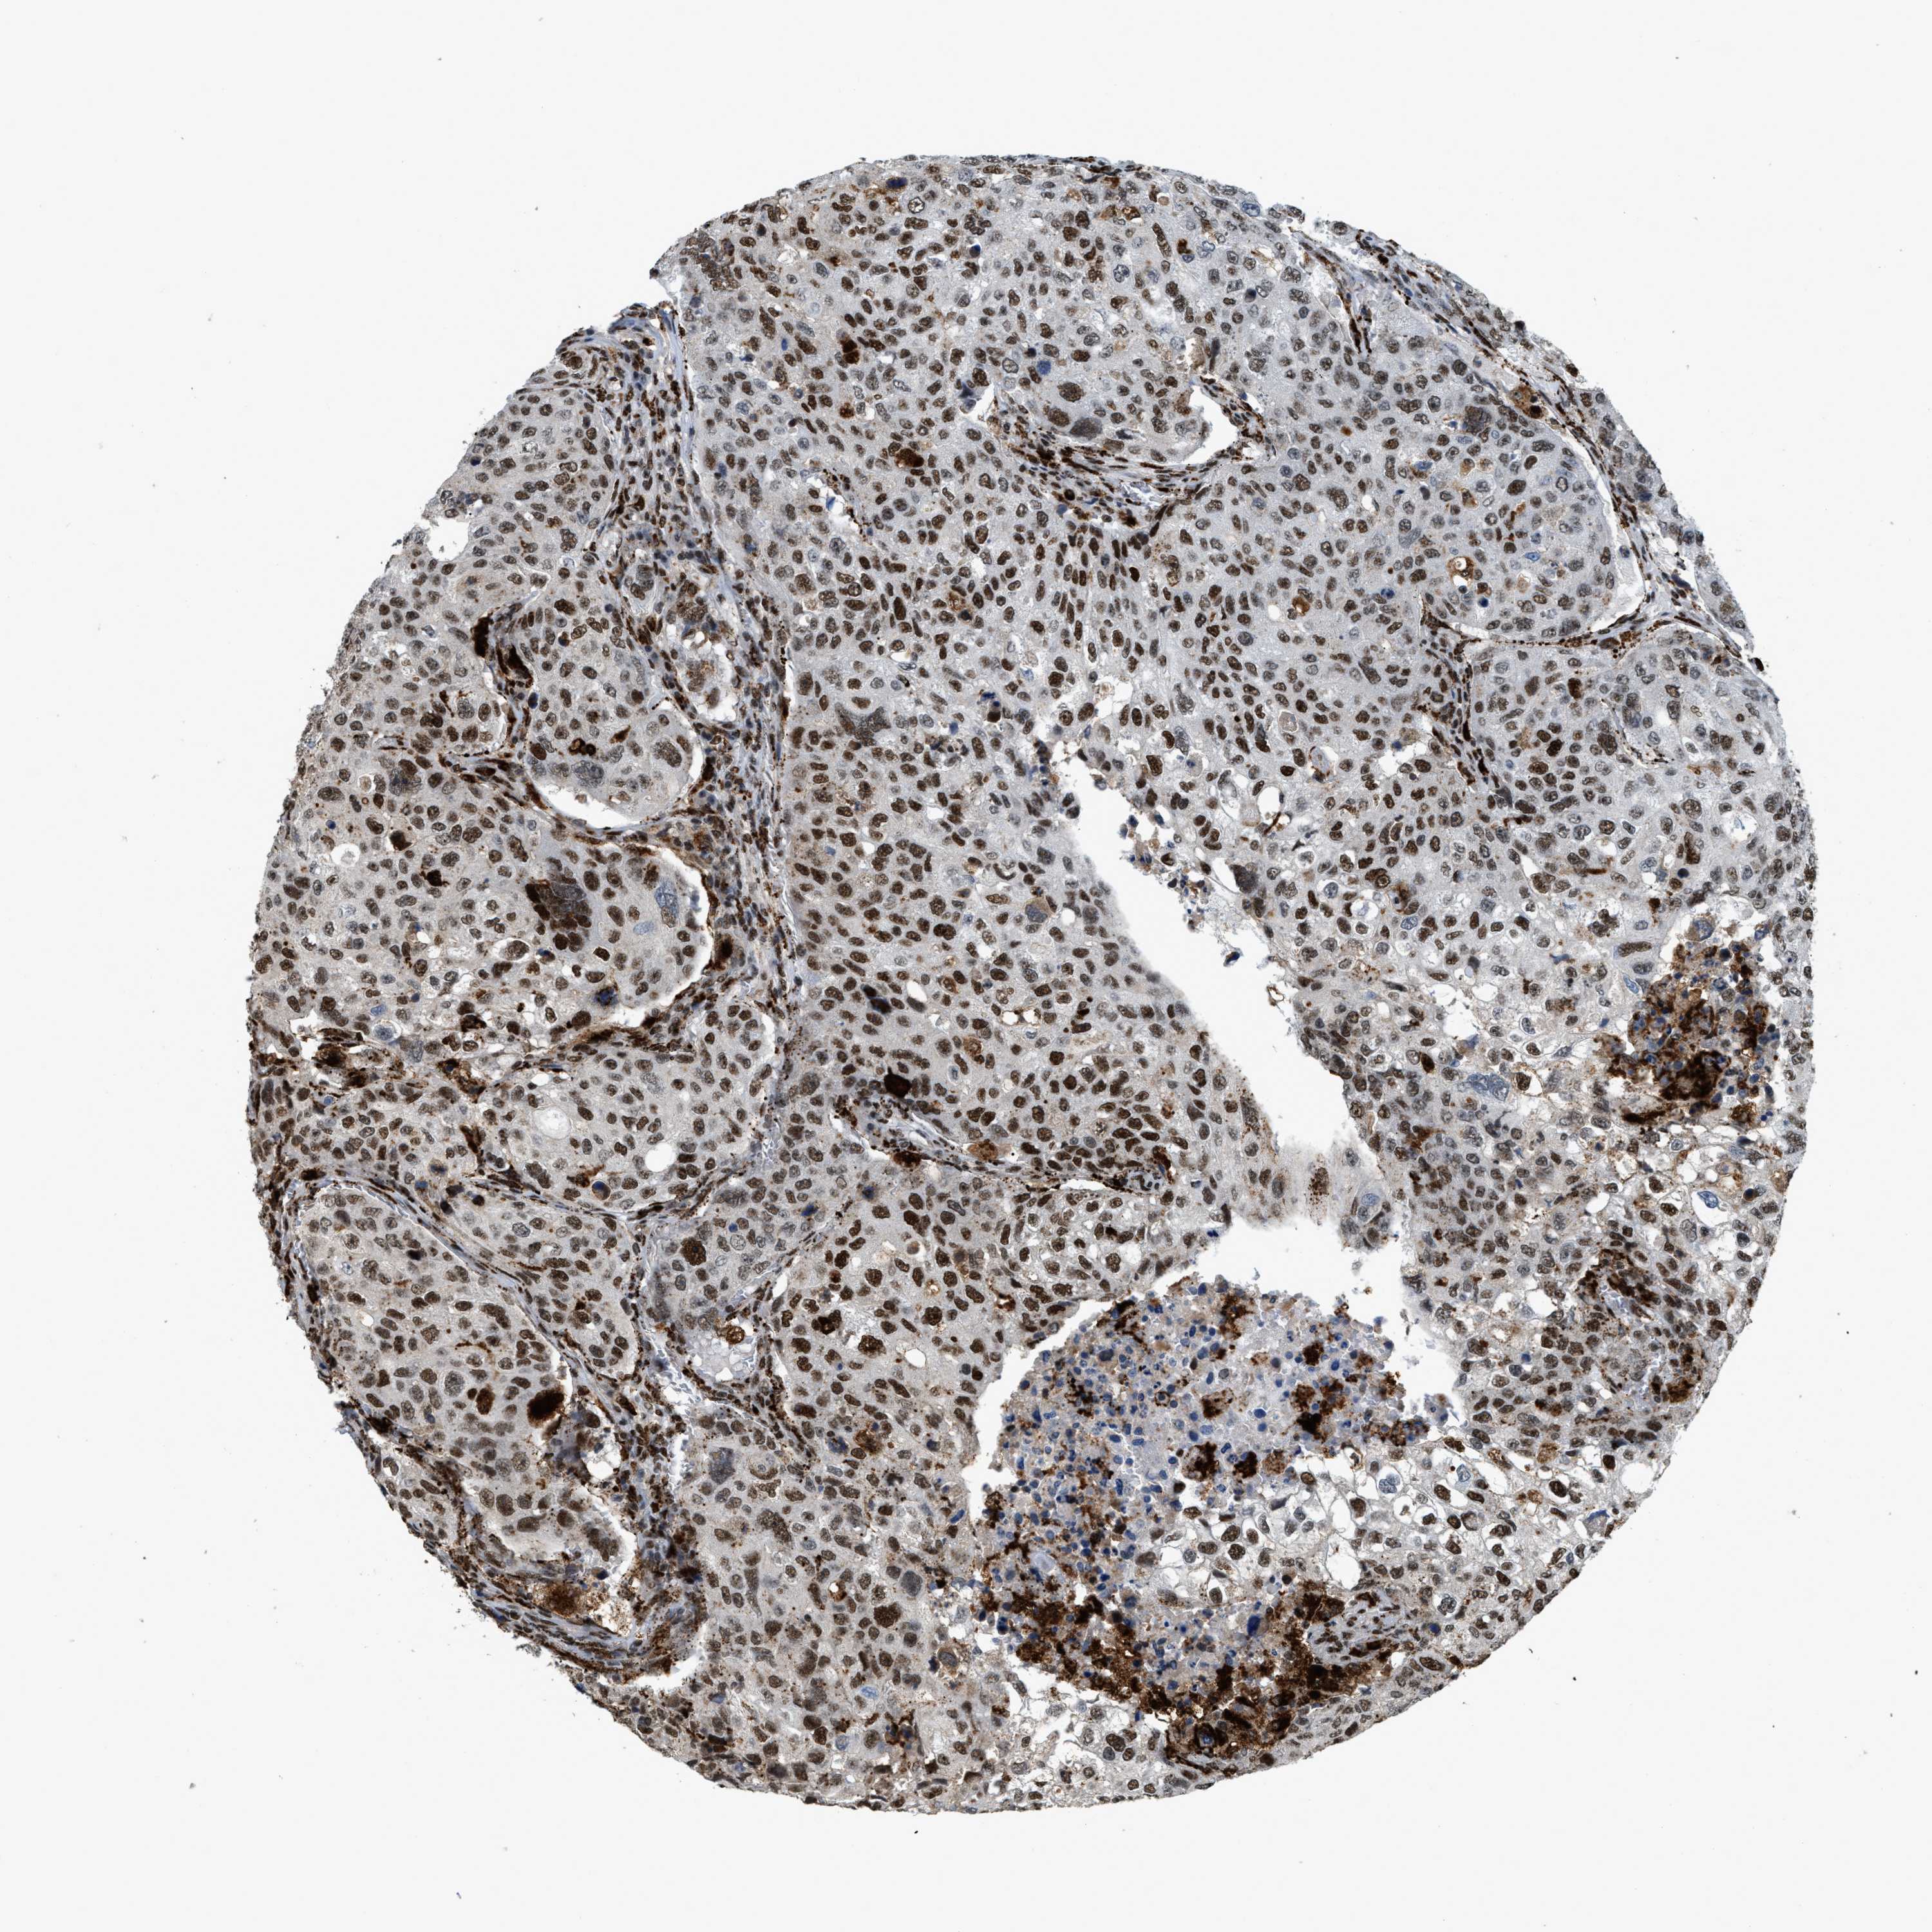

UROTHELIAL CANCER - Protein expressioni

A mouse-over function shows sample information and annotation data. Click on an image to view it in a full screen mode. Samples can be filtered based on level of antibody staining by selecting one or several of the following categories: high, medium, low and not detected. The assay and annotation is described here.

Note that samples used for immunohistochemistry by the Human Protein Atlas do not correspond to samples in the TCGA dataset.

Antibody stainingi

Antibody staining in the annotated cell types in the current human tissue is reported as not detected, low, medium, or high, based on conventional immunohistochemistry profiling in selected tissues. This score is based on the combination of the staining intensity and fraction of stained cells.

Each image is clickable and will lead to virtual microscopy that enables deeper exploration of all samples and also displays staining intensity scores, fraction scores and subcellular localization as well as patient and tissue information for each sample.

Antibody HPA019841

Antibody HPA019859

Antibody HPA029912

Staining

High

Medium

Low

Not detected

Intensity

Strong

Moderate

Weak

Negative

Quantity

>75%

75%-25%

<25%

None

Location

Urothelial carcinoma, Low grade

Urothelial carcinoma, High grade